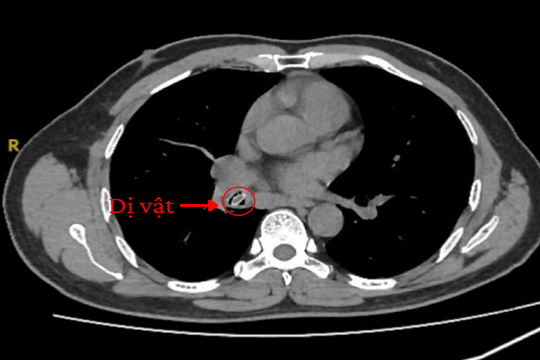

Bác sĩ khuyến cáo: Ho dai dẳng suốt một năm trời do hóc dị vật